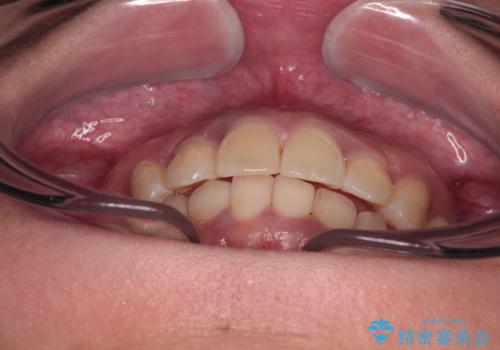

前歯のデコボコと隠れてしまう下顎前歯 インビザラインですっきりと改善

- 前歯のデコボコと、深い咬み合わせにより前歯が隠れていることを気にして来院された患者様です。

インビザライン発注後に長期滞在先から2年間ほど帰国することができず、インビザラインの有効期限内に終了できるのか不安でしたが、矯正治療開始後は十分な装着時間を達成され、1年未満の期間で無事に終えることができました。